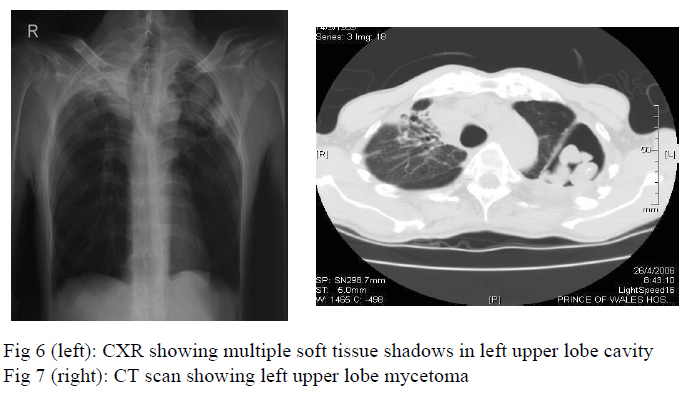

Two months later, chest radiograph showed a large cavity at the left upper lobe with multiple soft tissue shadows inside the cavity (fig 6) whereas CT thorax showed evidence of mycetoma formation at the left upper lobe (fig 7). In view of persistent haemoptysis and radiological deterioration, voriconazole 200mg daily was started in June, 2006 and the anti-tuberculosis treatment was changed from isoniazid and rifampicin as maintenance therapy to isoniazid, ethambutol, pyrazinamide for 3 more months. He was referred for surgical treatment of symptomatic mycetoma.